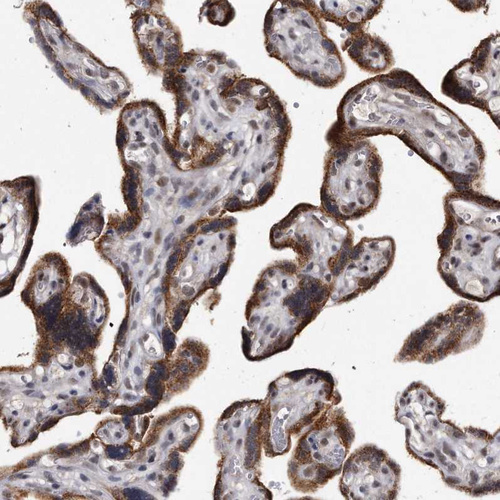

Immunohistochemical staining of human testis shows moderate cytoplasmic positivity in cells in seminiferous ducts and leydig cells.